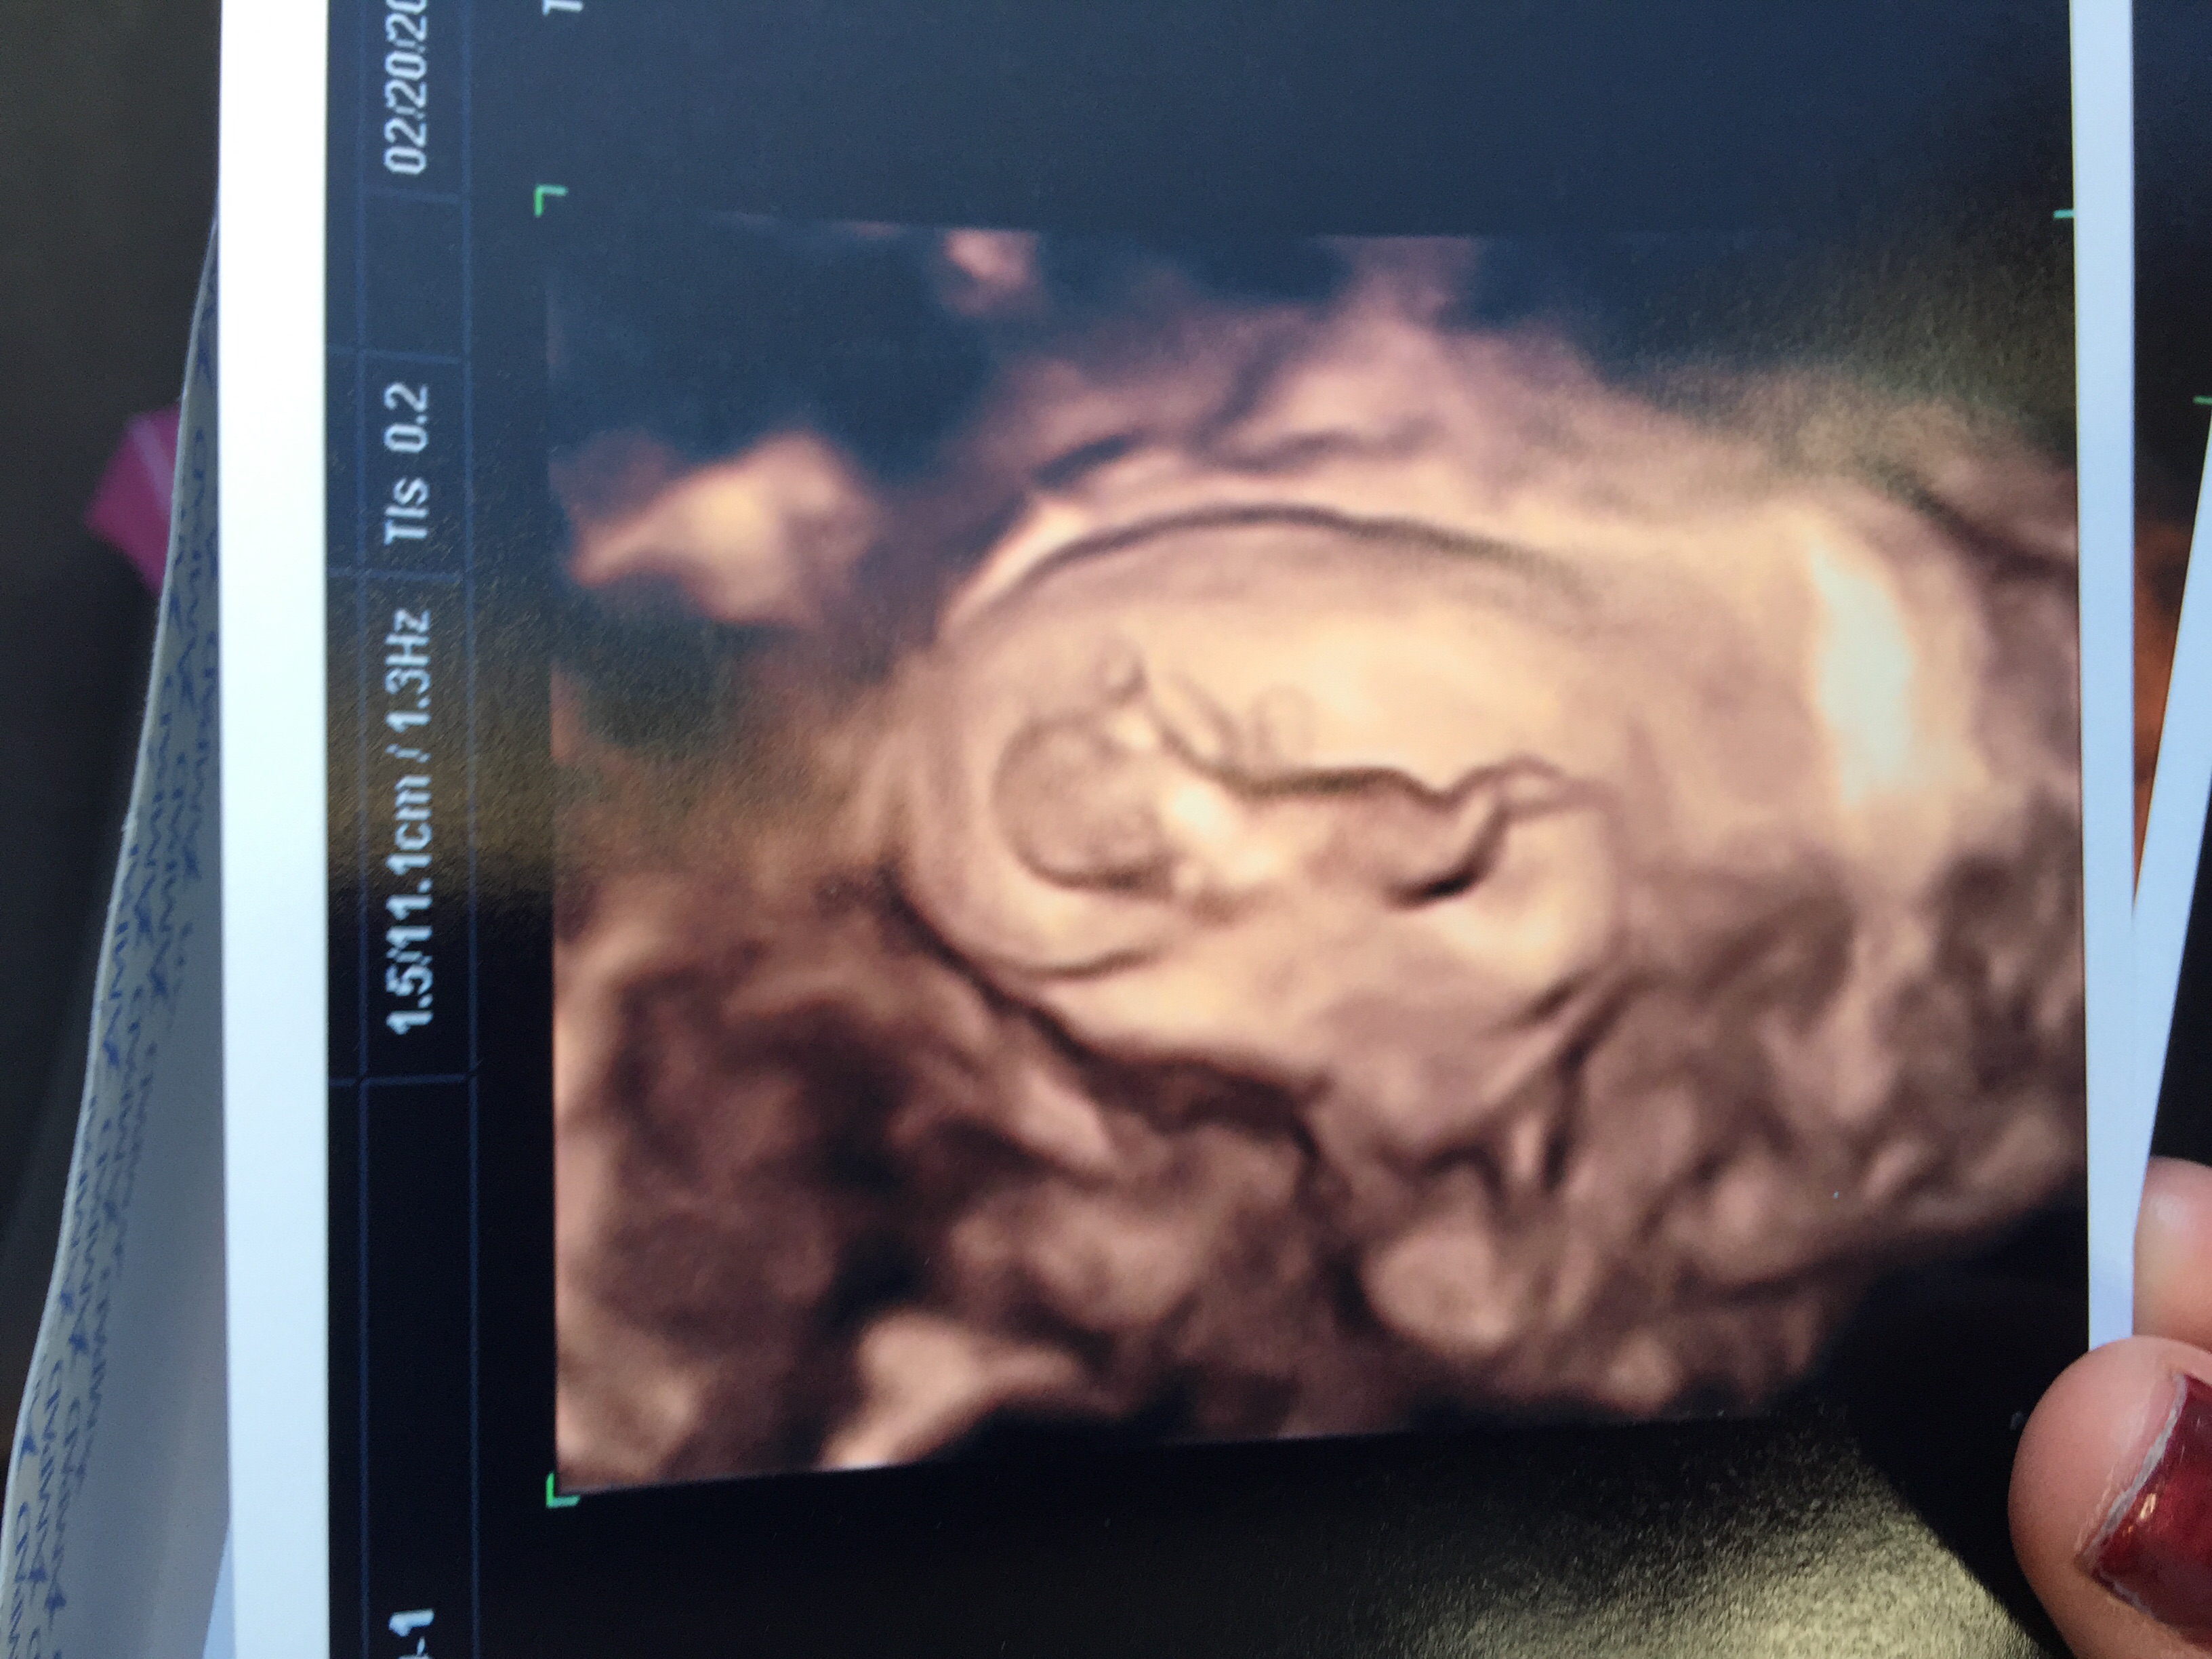

Look at my 11 weeks 1 day ultrasound

so cool thought I'd share

The baby moving